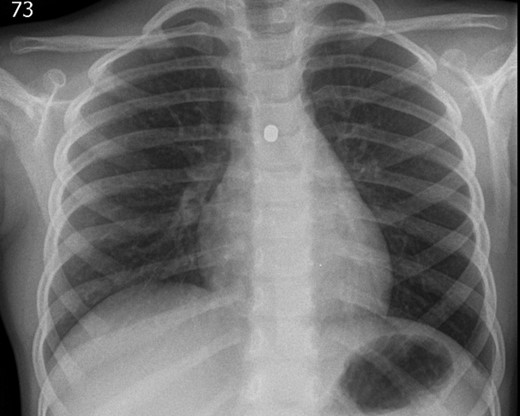

A 3-year-old girl was referred to the asthma clinic with a 3-month history of morning cough and wheeze. She was seen multiple times by her general practitioner (GP) who initially diagnosed her with upper respiratory tract infection. Her symptoms persisted despite salbutamol inhaler treatment so the GP organised a chest x-ray (CXR) (Fig. 1). It was reported that the left lung was translucent with reduced peripheral lung markings: finding consistent with asthma with bronchial plugging or a post infective bronchiolitis. It also showed a round radio-opaque FB over the left main bronchus. However, this was labelled as ‘Clothing Artefact’ on the actual radiograph and therefore did not alarm the GP or the reporting radiologist. A repeated PA CXR (Fig. 2) was undertaken in the asthma clinic where all clothes and hair were removed from the thorax. This confirmed the presence of a metallic FB in the left main bronchus and the patient was immediately admitted for bronchoscopy and removal of the FB.

The repeated posterior–anterior CXR taken with all clothes and hair removed from the thorax of the patient. It confirmed the presence of a metallic foreign body in the left main bronchus.